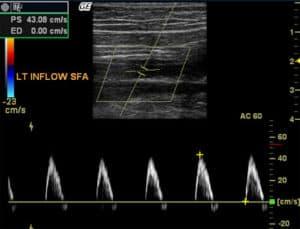

The evaluation of lower extremity bypass grafts with color Doppler and duplex ultrasound is critical for early detection of stenoses and prevention of occlusion. These imaging modalities are non-invasive, reproducible, and ideal for monitoring graft function, improving outcomes through timely intervention.

to discuss the criteria for a normal color Doppler and duplex ultrasound examination